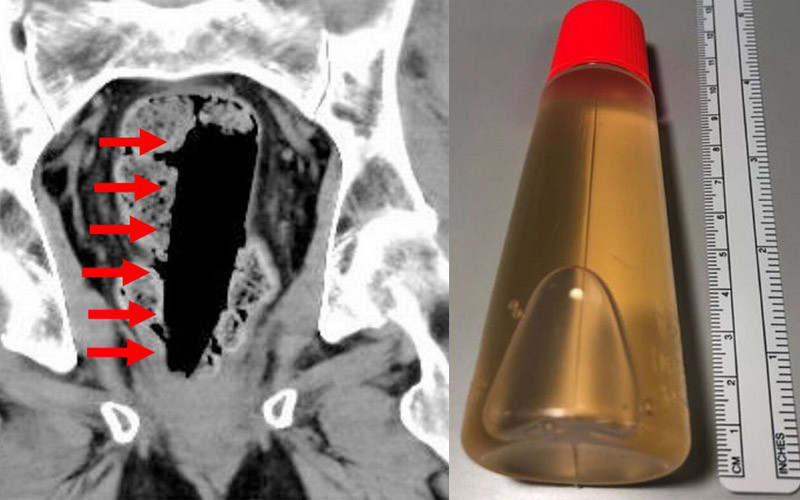

Kết quả chụp CT cho thấy, trong trực tràng có hộp đựng keo kích thước 35x35x120mm. Khi lấy nó ra, các bác sỹ nhận thấy vẫn còn nguyên chất keo lỏng bên trong hộp.

Kết quả chụp CT cho thấy một hộp keo ở phía trong hậu môn người bệnh. (Ảnh: Jam Press)

Lọ keo đã được lấy ra. (Ảnh: Jam Press)